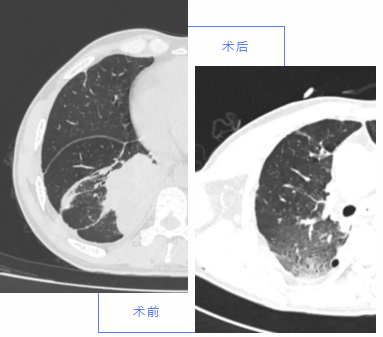

肺癌患者

男性,因近1个月连续咳嗽,并出现加重胸闷、咳血症状,收治我院胸外科。

完善相关检查后,胸外科医师科内进行病情讨论,经过认真研究、仔细分析,诊断可能为右肺下叶恶性肿瘤。行传统开胸手术损伤大,恢复慢,与患者及家属沟通病情,经患者同意,决定行胸腔镜微创手术治疗。整个手术历时2小时,出血少。术后患者恢复良好,1周后治愈出院。